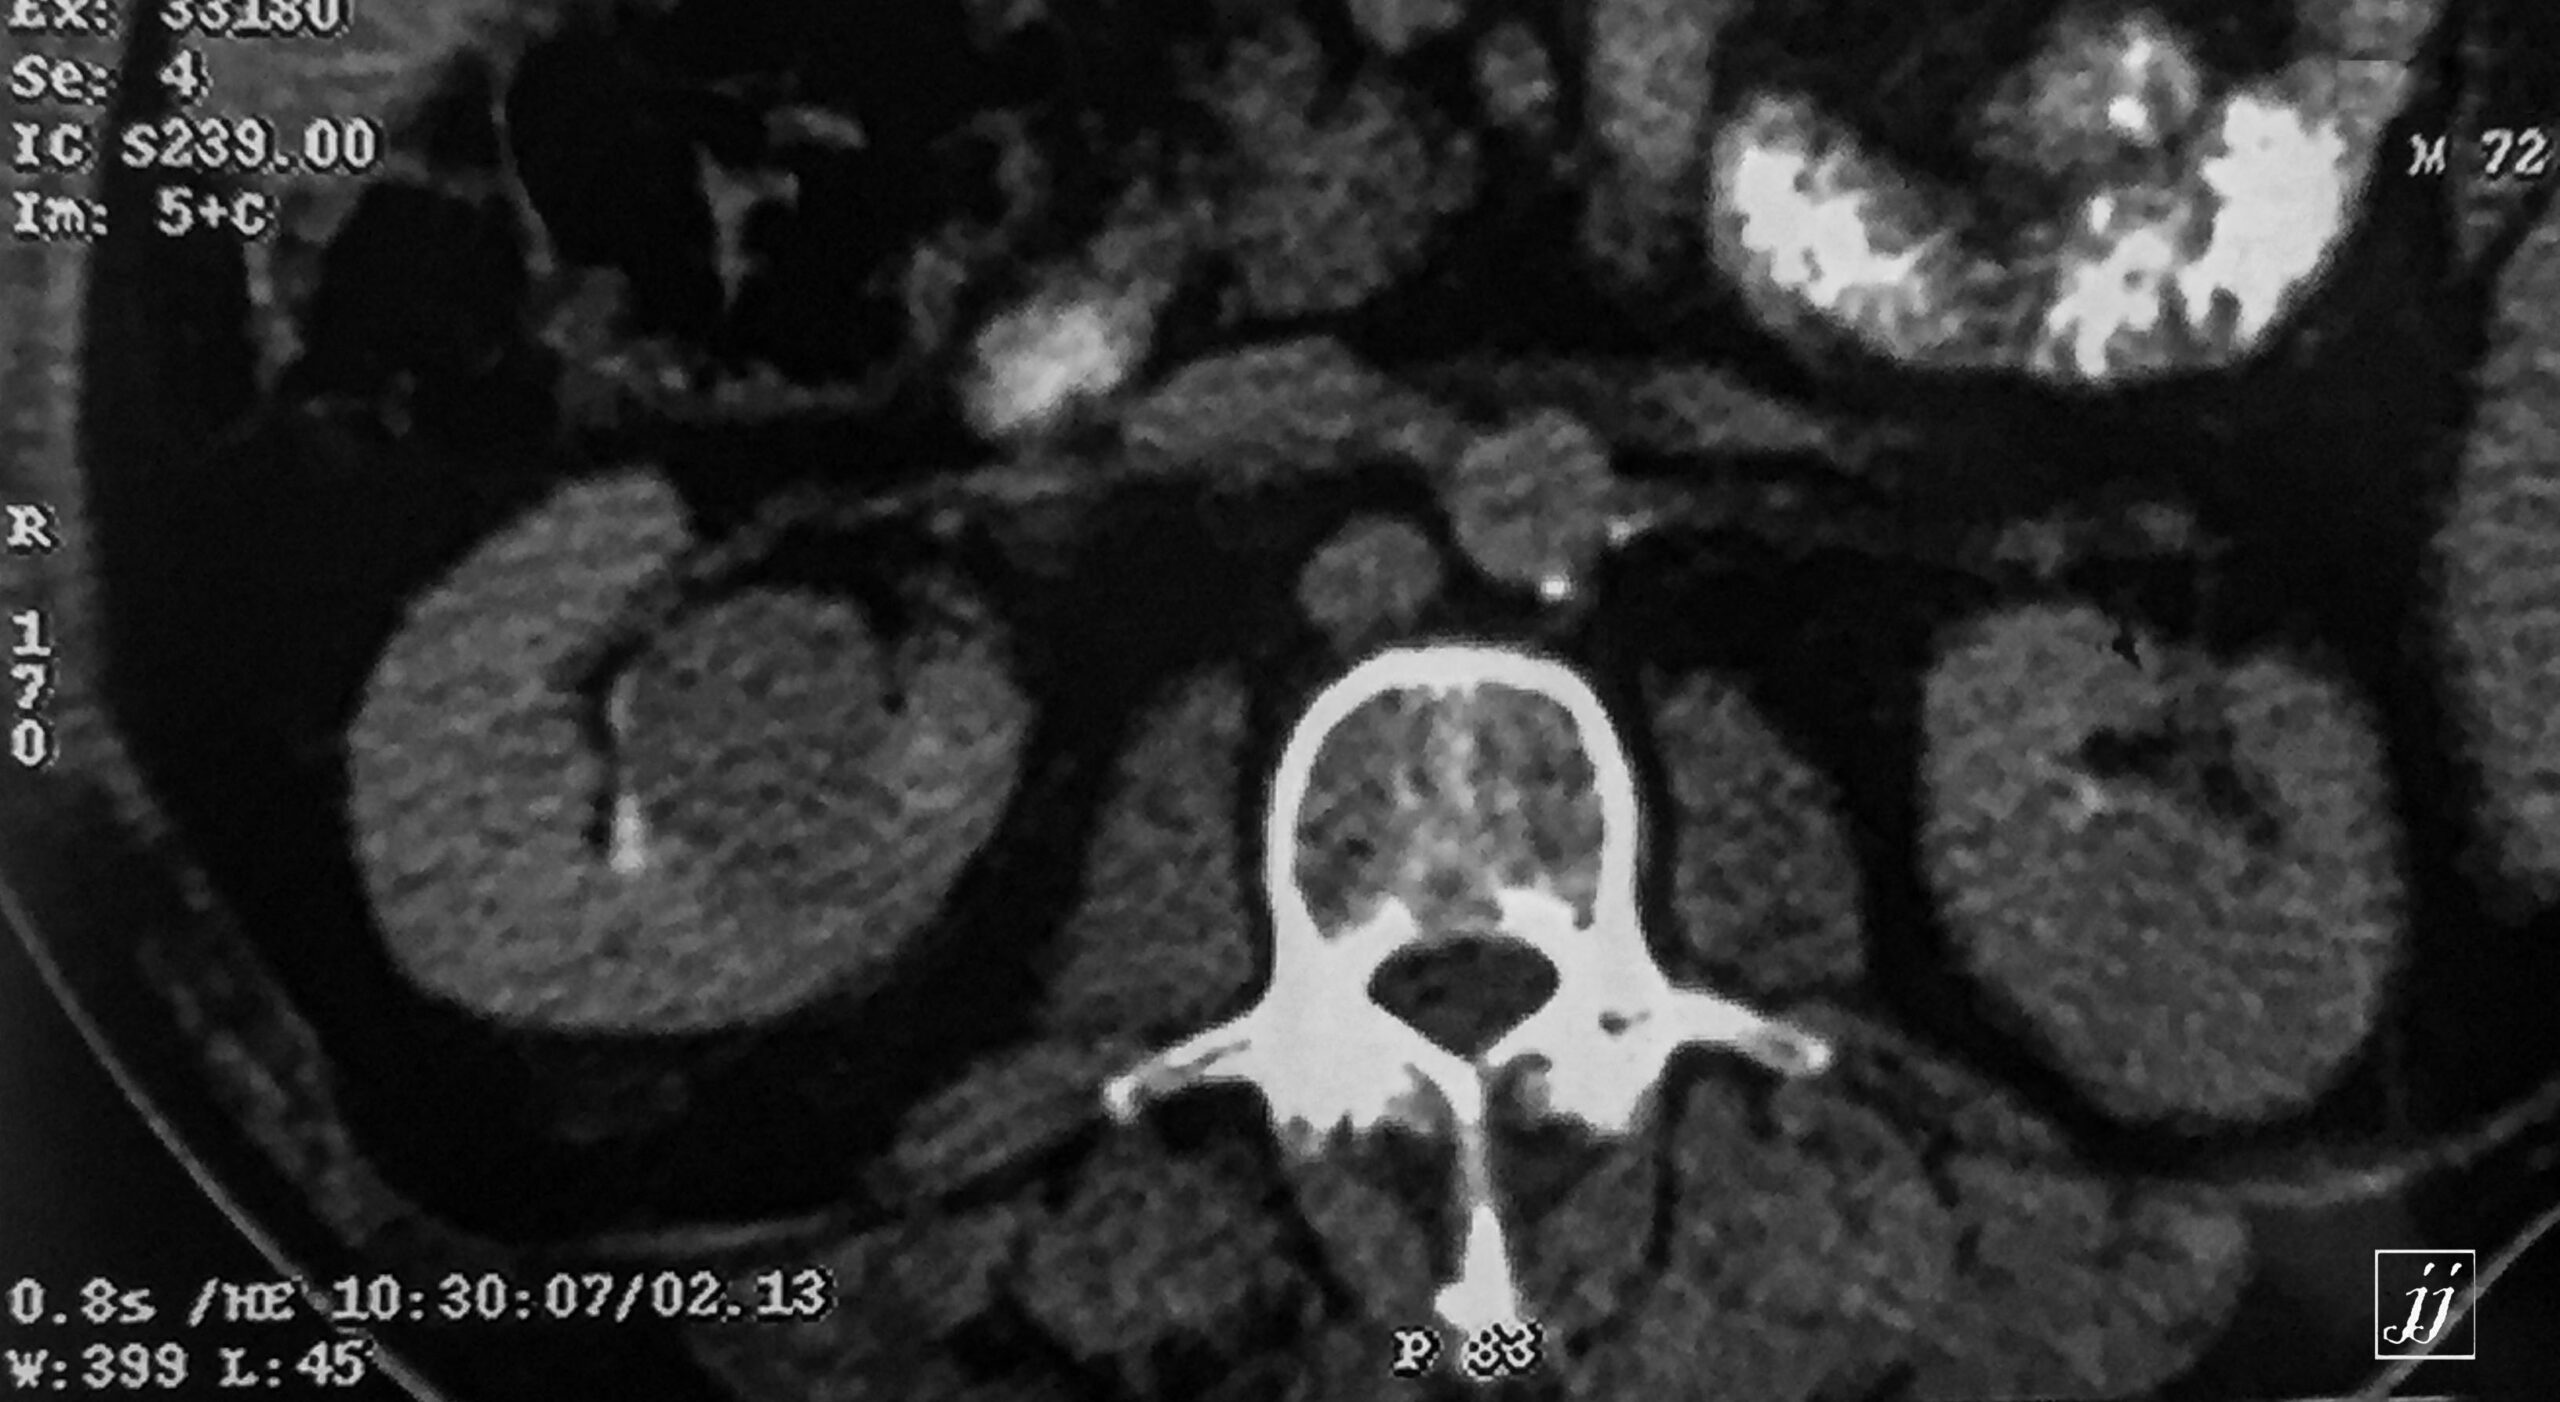

Abdomen- bi lateral kidney masses (13)